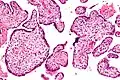

Micrograph of villitis of unknown etiology. H&E stain.

Histopathology

Histomorphologically, VUE is characterized by a lymphocytic infiltrate of the chorionic villi without a demonstrable cause. Plasma cells should be absent; the presence of plasma cells suggests an infective etiology, e.g. CMV infection.